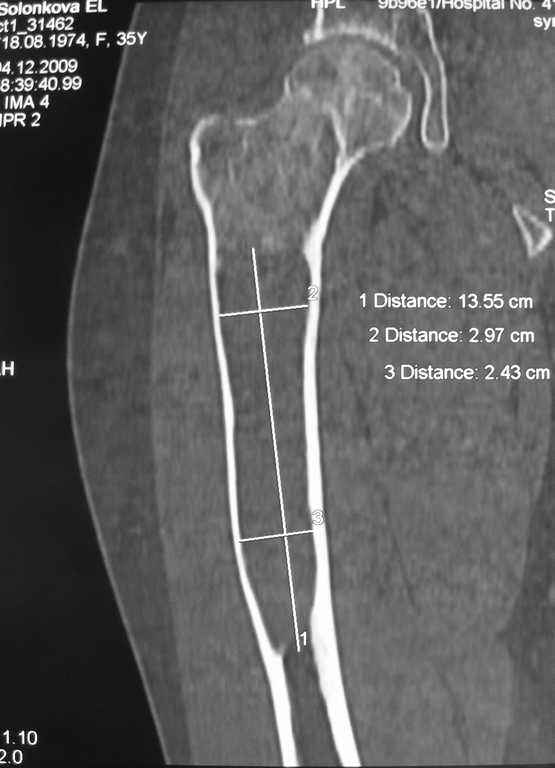

Елена,

При наличии в института сосудистых хирургов, как альтернативный метод можно было бы предложить графт как показано на снимке.

Не мой случай, но красиво!